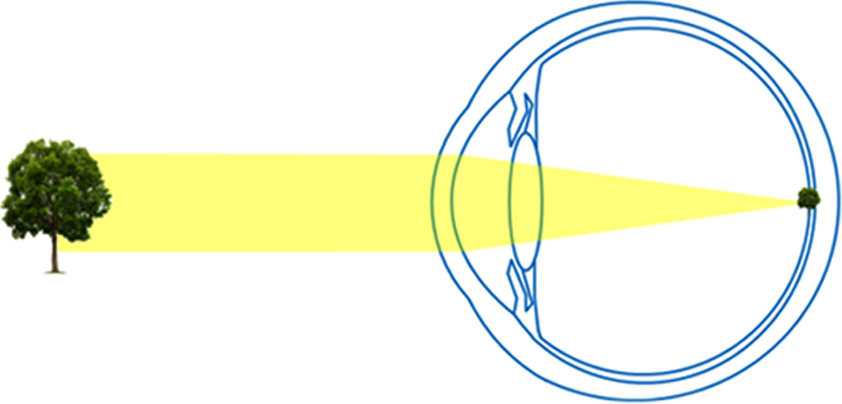

L'accommodation est le mécanisme permettant à l'oeil de voir à plusieurs distances. Ce mécanisme repose sur la capacité du cristallin à se déformer et à ajuster sa puissance.

En effet, si l'oeil était statique, l'emmétrope (c'est-à-dire une personne sans défaut de vision) ne pourrait voir net que de loin car les images des objets proches se formeraient en arrière de la rétine et apparaîtraient donc floues.